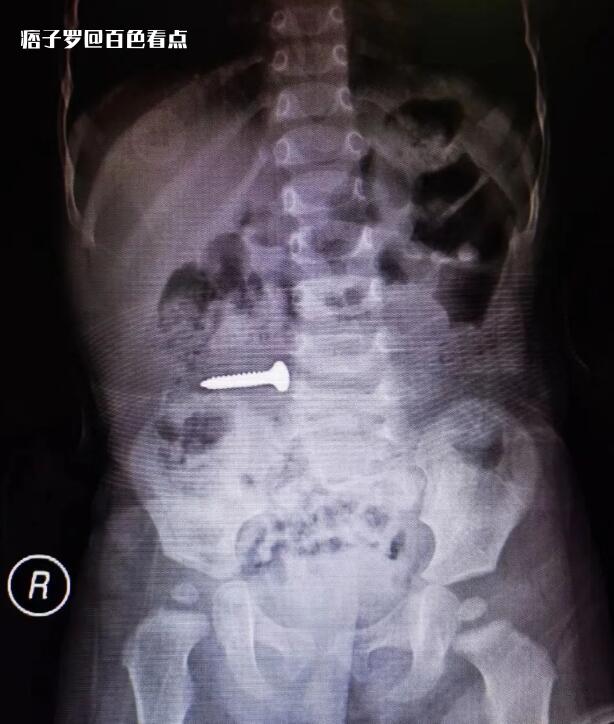

腹部X片显示:螺丝钉已滑至小肠上段

“平时光滑的小东西,可以考虑自行排出。但螺丝钉一端非常尖锐,且随着患儿胃肠蠕动已滑至小肠上段,如不及时取出,有刺破小肠导致腹膜炎腹腔感染的可能,需要尽快手术取出。”胃肠小儿外科主治医师覃立龙说。在取得患儿家属同意后,胃肠小儿外科专家团队当即制定手术方案,在螺丝钉滑入更深位置之前,通过腹腔镜找到异物,从肚脐小切口成功将其取出。